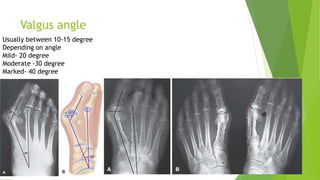

Valgus angle

Usually between 10-15 degree

Depending on angle

Mild- 20 degree

Moderate -30 degree

Marked- 40 degree